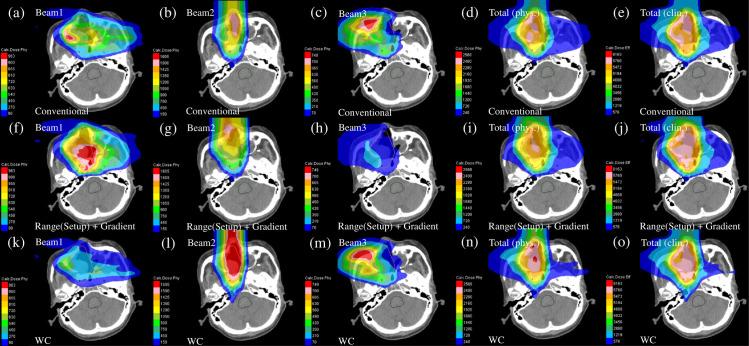

Currently, treatment planning systems (TPSs) that can compute the intensities of intensity-modulated carbon-ion therapy (IMCT) using scanned carbon-ion beams are limited. In the present study, the computational efficacy of the newly designed IMCT algorithms was analyzed for the first time based on the mixed beam model with respect to the physical and biological doses; moreover, the validity and effectiveness of the robust radiobiological optimization were verified. A dose calculation engine was independently generated to validate a clinical dose determined in the TPS. A biological assay was performed using the HSGc-C5 cell line to validate the calculated surviving fraction (SF). Both spot control (SC) and voxel-wise worst-case scenario (WC) algorithms were employed for robust radiobiological optimization followed by their application in a Radiation Therapy Oncology Group benchmark phantom under homogeneous and heterogeneous conditions and a clinical case for range and position errors. Importantly, for the first time, both SC and WC algorithms were implemented in the integrated TPS platform that can compute the intensities of IMCT using scanned carbon-ion beams for robust radiobiological optimization. For assessing the robustness, the difference between the maximum and minimum values of a dose-volume histogram index in the examined error scenarios was considered as a robustness index. The relative biological effectiveness (RBE) determined by the independent dose calculation engine exhibited a -0.6% difference compared with the RBE defined by the TPS at the isocenter, whereas the measured and the calculated SF were similar. Regardless of the objects, compared with the conventional IMCT, the robust radiobiological optimization enhanced the sensitivity of the examined error scenarios by up to 19% for the robustness index. The computational efficacy of the novel IMCT algorithms was verified according to the mixed beam model with respect to the physical and biological doses. The robust radiobiological optimizations lowered the impact of range and position uncertainties considerably in the examined scenarios. The robustness of the WC algorithm was more enhanced compared with that of the SC algorithm. Nevertheless, the SC algorithm can be used as an alternative to the WC IMCT algorithm with respect to the computational cost.

目前,能够使用扫描碳离子束计算强度调制碳离子治疗(IMCT)强度的治疗计划系统(TPS)有限。在本研究中,首次基于混合束模型分析了新设计的 IMCT 算法在物理和生物剂量方面的计算功效,同时验证了稳健放射生物学优化的有效性和实用性。为了验证 TPS 中确定的临床剂量,独立生成了一个剂量计算引擎。使用 HSGc-C5 细胞系进行了生物测定,以验证计算的存活分数(SF)。对于稳健放射生物学优化,使用点控制(SC)和体素最差情况(WC)算法,然后将其应用于均匀和非均匀条件下的放射治疗肿瘤学组基准体模以及范围和位置误差的临床病例中。重要的是,首次在可以使用扫描碳离子束计算 IMCT 强度的集成 TPS 平台中实现了 SC 和 WC 算法,用于稳健放射生物学优化。为了评估稳健性,将检查的误差情况下剂量-体积直方图指数的最大值和最小值之间的差异作为稳健性指数。由独立剂量计算引擎确定的相对生物效应(RBE)与在等中心处由 TPS 定义的 RBE 相比,差异为-0.6%,而测量和计算的 SF 相似。无论对象如何,与传统的 IMCT 相比,稳健放射生物学优化将检查的误差情况下的稳健性指数的敏感性提高了多达 19%。根据物理和生物剂量,通过混合束模型验证了新型 IMCT 算法的计算功效。稳健放射生物学优化在检查的场景中大大降低了范围和位置不确定性的影响。与 SC 算法相比,WC 算法的稳健性得到了更多的增强。然而,就计算成本而言,SC 算法可以作为 WC IMCT 算法的替代方案。